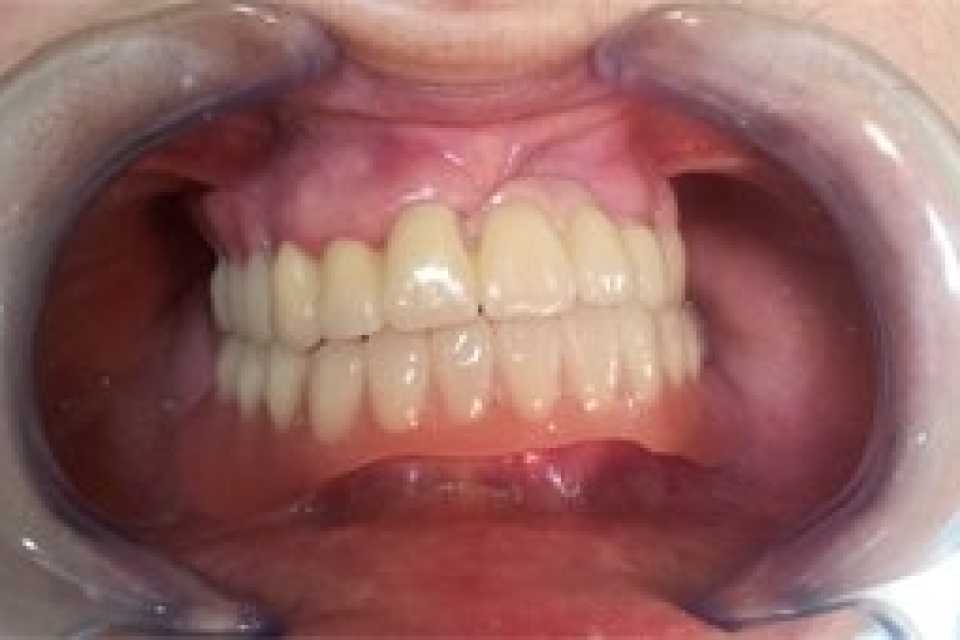

Proteza scheletata superioara pe telescoape si inferioara pe capse

Cazul 21: Proteze scheletate cu sisteme speciale de prindere

Protezele scheletale cu sisteme speciale de prindere reprezintă soluții de tratament care necesită înaltă specializare atât a medicului stomatolog, cât și a tehnicianului dentar, fiind recomandate în special pacienților cu edentații extinse, însă care prezintă încă suficienți dinți naturali rămași pe care se pot realiza astfel de lucrări dentare.